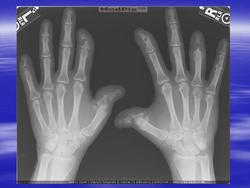

Артрит